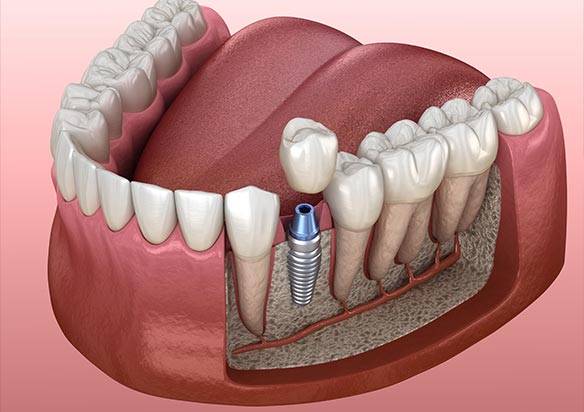

Zubni implantati – Implantati se u stomatologiji koriste kako bi se nadomjestio jedan zub i/ili svi zubi. Mogu se ugraditi u obje čeljusti na mjesto zubnog korijena. Izrađeni su od titana i ne izazivaju alergijske reakcije.